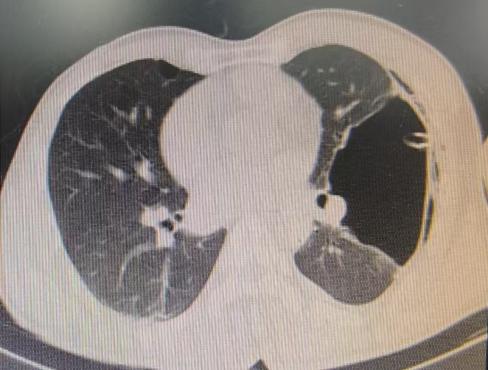

面对这一复杂状况,陈教授凭借丰富的经验果断调整手术方案。在确保安全的前提下,对可疑病灶进行了精准活检取样,随后精准置入胸腔引流管。术后即刻CT确认引流管位置良好,同时制定了严密的术后管理方案:每日监测引流量及肺复张情况,若引流量持续减少且肺大疱逐渐缩小,则按计划拨管;若肺大疱未明显缩小,则考虑拔除引流管后转外科进行胸膜剥离术。

术后复查CT显示,肺大疱明显缩小,患者胸闷症状显著减轻。整个手术过程进展顺利,患者术后恢复良好。

(术前左肺肺大疱明显-术后肺大疱逐渐缩小闭合)